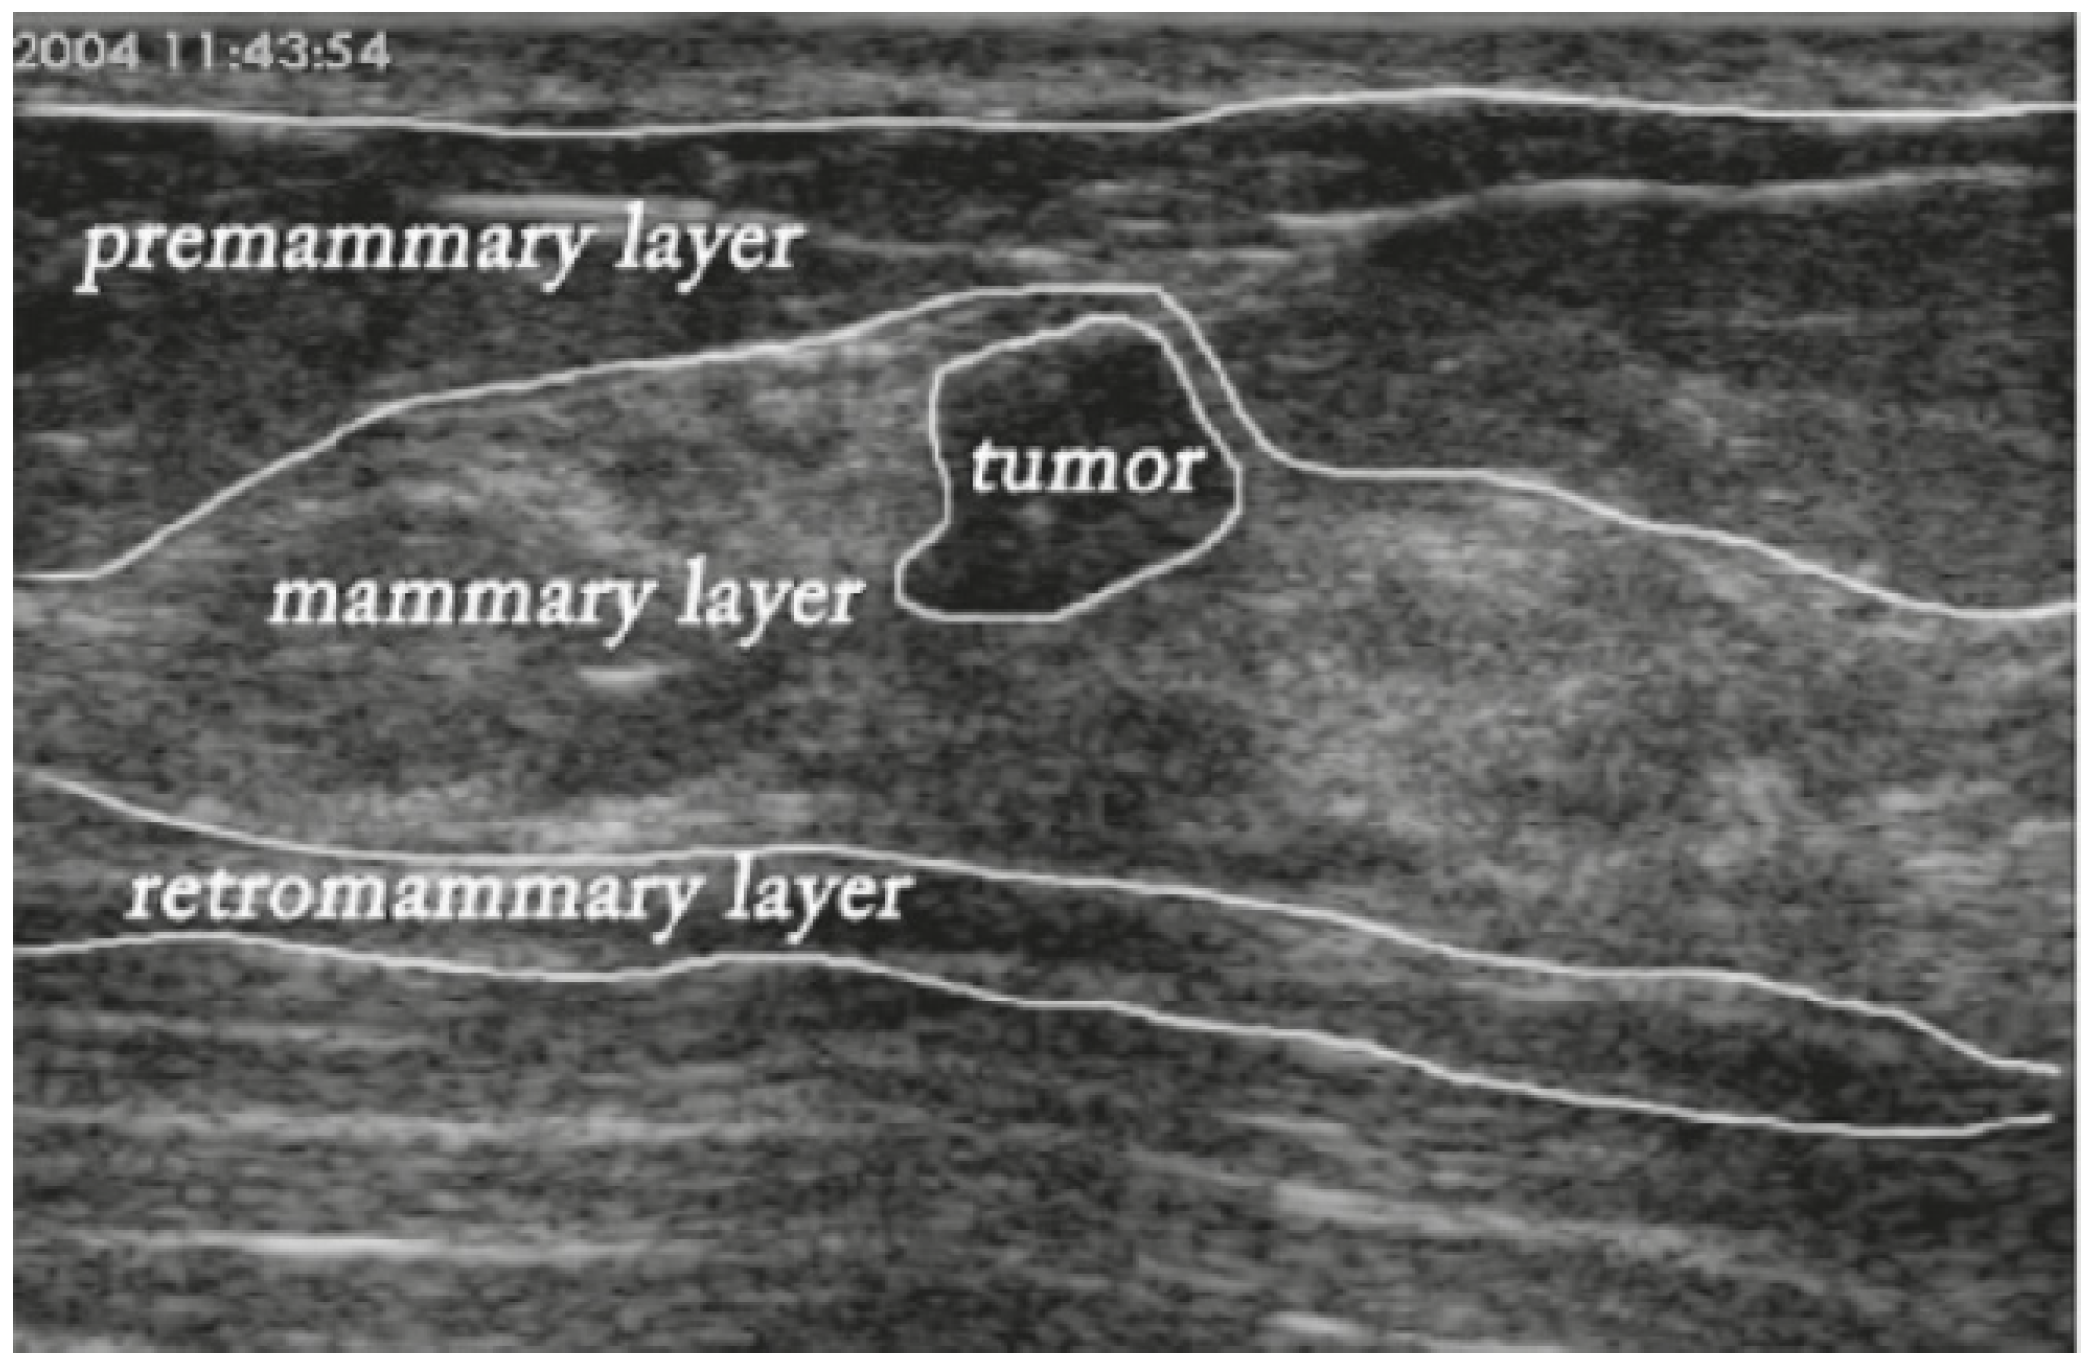

To overcome this problem, we redesigned the encoder by applying row-column-wise kernels. The small square kernels in STAN constructed feature maps using only square image regions. The motivation for the design is because BUS images are composed of vertically stacked tissue layers (Figure 3). Applying row-column-wise kernels in CNNs can avoid calculating features using image regions from multiple anatomical layers and produce more accurate and meaningful feature maps. In addition, in this study, ESTAN is compared with nine state-of-the-art approaches on three datasets, while STAN was compared with only three state-of-the-art approaches on two datasets.

Figure 3.

Major breast layers of a sample BUS image.

In this paper, we extend STAN and propose a new architecture, namely the Enhanced Small Tumor-Aware Network or ESTAN, to achieve robust segmentation for tumors of different sizes. The new architecture has two encoder branches. The basic encoder has five blocks and learns features at different scales. The ESTAN encoder applies row-column-wise kernels to adapt to the breast anatomy during feature learning. Specifically, the human breast anatomy consists of four main layers: skin, premammary (subcutaneous fat), mammary, and retromammary layers [32]. Each layer is characterized by a distinct texture and corresponding echo patterns in ultrasound images. The tissue layers in BUS images appear vertically stacked, with similar echo patterns propagating horizontally across images. Breast pathology originates predominantly in the mammary layer. The row-column-wise kernels were designed to learn the breast tissue structure and thus improve detecting small tumor representations in BUS images. In the decoder, each block has three skip connections that fuse rich contextual features from the two encoders. The contextual features are robust to different tumor sizes and help distinguish tumor regions from normal regions.